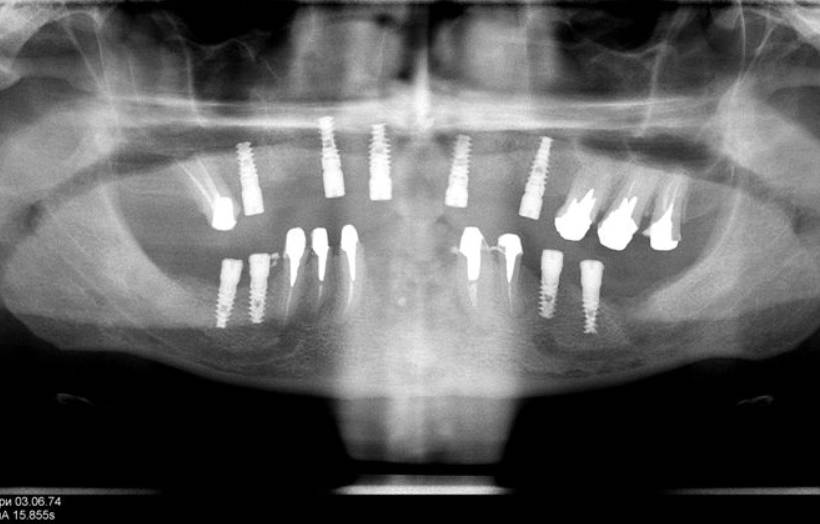

Dental Rehabilitation Using Alpha Dent Implant in Case of Reconstructed Mandible after Excision of Ossifying Fibroma

Dental Rehabilitation Using Alpha Dent Implant in Case of Reconstructed Mandible after Excision of Ossifying Fibroma Dr. Parit Ladani MDS